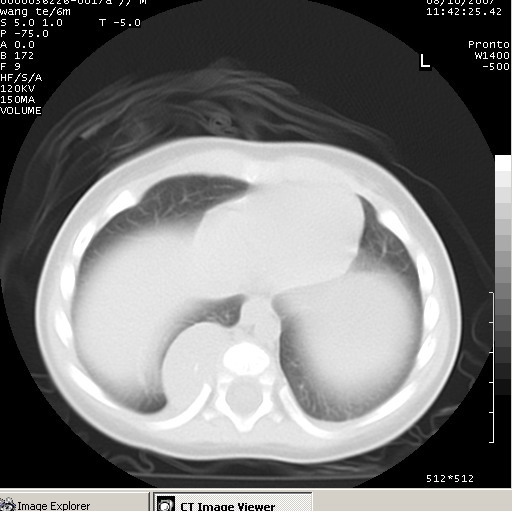

患儿男、6个月,因咳嗽三天曾拍胸片考虑肺部感染,这是在胸片后约一周左右作的ct。

后纵隔神经元性肿瘤。

右下肺纵隔旁软组织密度影,边界清楚,内见点状高密度影。支持考虑:神经源性肿瘤!

右下肺纵隔旁软组织密度影,宽基底紧贴胸椎与肋骨,边界清楚,内见点状高密度影。支持考虑:神经源性肿瘤!肺隔离症待排

后纵隔占位性病变,考虑为神经源性肿瘤可能性大。

典型的神经源性肿瘤

支持神经源性肿瘤,有肋骨破坏。